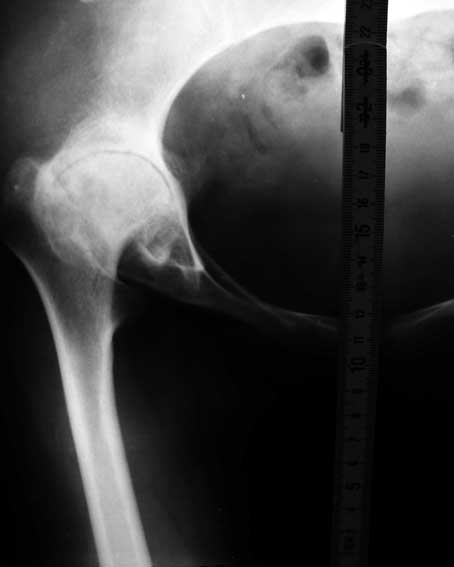

Уважаемые коллеги! Хотелось бы получить совет по тактике лечения. Обратилось 2 девушки - 25 и 26 лет. У обеих грубейшие сгибательные контрактуры тазобедренных суставов.

В одном случае после многократных операций в детстве по поводу врожденных вывихов бедер, в другом - ревматоидный полиартрит. Обе очень маленькие.

Перепробовал все имеющиеся виды шаблонов ножекпротезов - не подходят. На картинке линейка как масштаб - ширина 15мм.

Посмотрите на вертлужную впадину при ревматоидном артрите - вертлужная впадина не на месте, нет кости да и качество кости при ревматоидном артрите

плохое. Эндопротезирование в таком случае поможет на очень короткий срок.